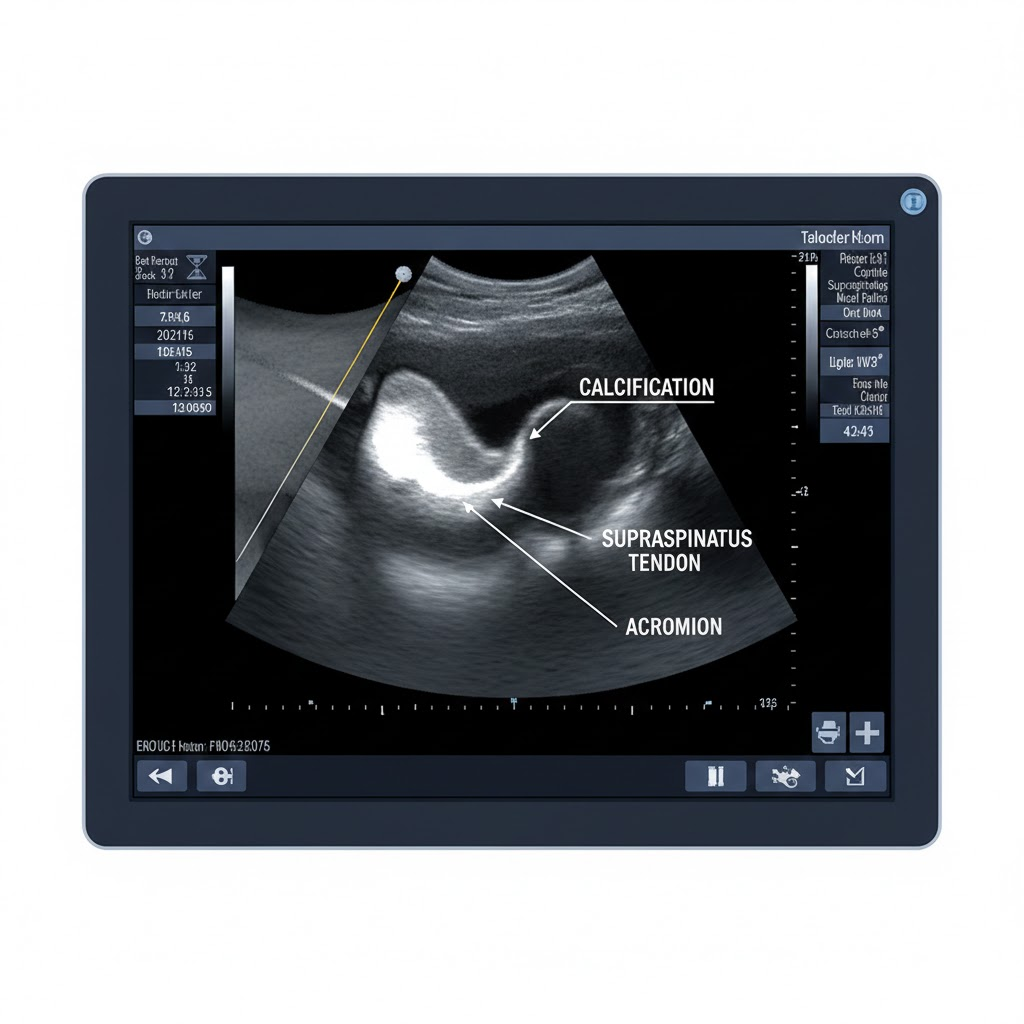

③ 초음파 유도하 석회 쇄석술 (Barbotage)

초음파로 석회의 위치를 실시간으로 확인하면서 가느다란 주삿바늘로 석회를 잘게 깨뜨리거나, 생리식염수를 주입해 석회를 뽑아내는 시술입니다. 체외충격파만으로 해결되지 않는 크고 단단한 석회에 효과적입니다.